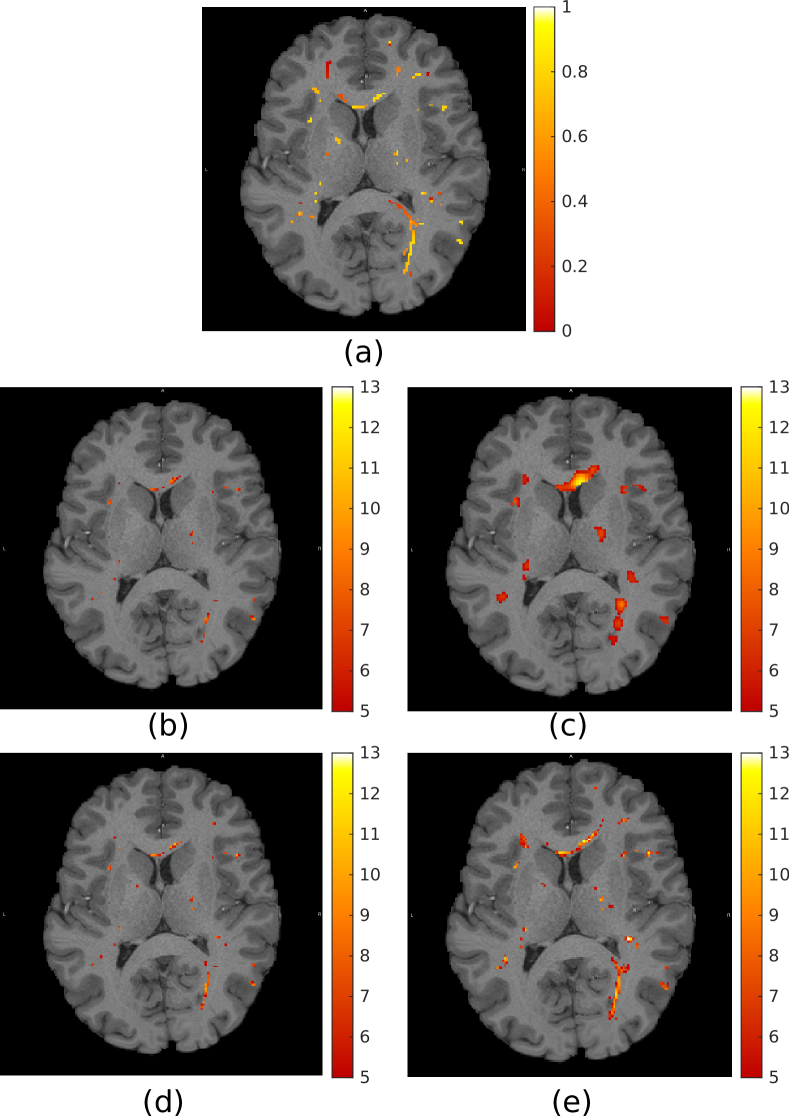

The 959595 semi-synthetic time-series phantoms were filtered using both isotropic Gaussian filtering and the proposed graph filtering approach. The resulting filtered volumes were subjected to a standard GLM-based activation mapping using the SPM toolbox. Figure 2 shows a comparison of the results obtained by using the various filtering methods. For small filter sizes, isotropic Gaussian filtering is capable of detecting the subtle shapes of the activations, but with reduced sensitivity compared to graph filtering. More activations are detected with larger filter sizes, but at the cost of diminished specificity. In contrast, the shapes of the activations detected through graph filtering are consistent across filter sizes.

The t-maps from all phantoms were thresholded at multiple levels and compared with the available ground truth activation patterns in order to produce ROC curves, which were then averaged across subjects. Figure 3 shows the average ROC curves for a variety of filter sizes. The best performance was achieved with Gaussian filters of FWHM=2FWHM2\text{FWHM}=2mm and graph filters of τ=1.4𝜏1.4\tau=1.4. The proposed filtering approach results in increased sensitivity and specificity across all tested filter sizes. Importantly, the performance of Gaussian filters of FWHM>2FWHM2\text{FWHM}>2mm is worse than without the application of any filtering.

Refer to caption

Fig. 2: (a) Example synthetic activation pattern. Dot-shaped activations extend linearly in the plane orthogonal to the image. (b)-(e) t-maps obtained from analysis conducted using: (b)-(c) isotropic Gaussian filtering, FWHM=2FWHM2\text{FWHM}=2mm and 666mm respectively; (d)-(e) graph filtering, τ=1.3𝜏1.3\tau=1.3 and 3.33.33.3 respectively. All t-maps thresholded at t=5𝑡5t=5 and overlaid on the T1 image of the corresponding subject.

Fig. 3: Average ROC curves from 959595 semi-synthetic phantoms. The proposed graph-filtering approach shows increased sensitivity and specificity across filter sizes.